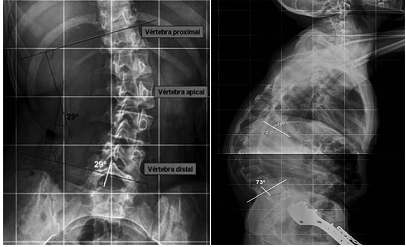

ESCOLIOSISLa escoliosis propiamente es la desviación lateral de la columna vertebral, asociada a rotación de los cuerpos vertebrales y alteración estructural de ellos. El término escoliosis proviene de una palabra griega que significa “torcido”. Se observa con frecuencia entre los 10 y 14 años y se inicia después de los 8 años, con un índice de 6 a 1 en las mujeres. Las personas pueden tener escoliosis a cualquier edad. El tipo más común es la escoliosis idiopática, o de origen desconocido, entre los niños de 10 a 12 años y al inicio de la adolescencia. Es a esta edad que los niños crecen con rapidez. Las niñas tienen una mayor predisposición a este tipo de escoliosis que los varones.

TRATAMIENTOEl tratamiento se inicia con la observación, ya que hay un importante número de casos que sólo hay que controlar y no requieren nunca tratamiento ortopédico. En general, a estos pacientes se les agrega ejercicios por medio de fisioterapia para mantener la columna flexible y mejorar la potencia muscular, abdominal y paravertebral. El siguiente grado en el tratamiento es el uso de corsé (el más empleado es el corsé de Milwaukee).

Está destinado a aquellos pacientes que están fuera del alcance ortopédico. Es decir pacientes con curvas sobre 45º, rígidas, mayores de 14 años, Risser 4, o que las curvas hayan aumentado dentro del corsé. El índice de Risser para estimación de maduración ósea, evalúa el grado de aparición del núcleo de osificación de la cresta ilíaca y su fusión al ala ilíaca, como se observa en la tabla. El grado de madurez ósea es otro de los factores pronósticos de la escoliosis idiopática, existiendo una mayor progresión de la curva en niños con un grado de Risser 0 ó 1, que en grados 2 a 5. La ventaja de utilizar este método es que las alas ilíacas están frecuentemente incluidas en la radiografía, por lo que sería innecesario contar con radiografías adicionales para la estimación de edad ósea(4). Indice de Risser

También requieren tratamiento quirúrgico para su corrección, aquellos pacientes que alcanzaron su maduración ósea y presentan curvas sobre 45º. El objetivo del tratamiento quirúrgico es estabilizar la columna ya que, de lo contrario, las curvas seguirían progresando y haciéndose cada vez más rígidas. El tratamiento quirúrgico pretende básicamente disminuir la magnitud de las curvas y mejorar las deformaciones estéticas. Esto se logra a través de la fusión de la zona de columna comprometida, luego de la corrección de las curvas con instrumental de distracción, compresión y desrotación de los cuerpos vertebrales, con sistemas de barras y ganchos o sistemas de Luque.